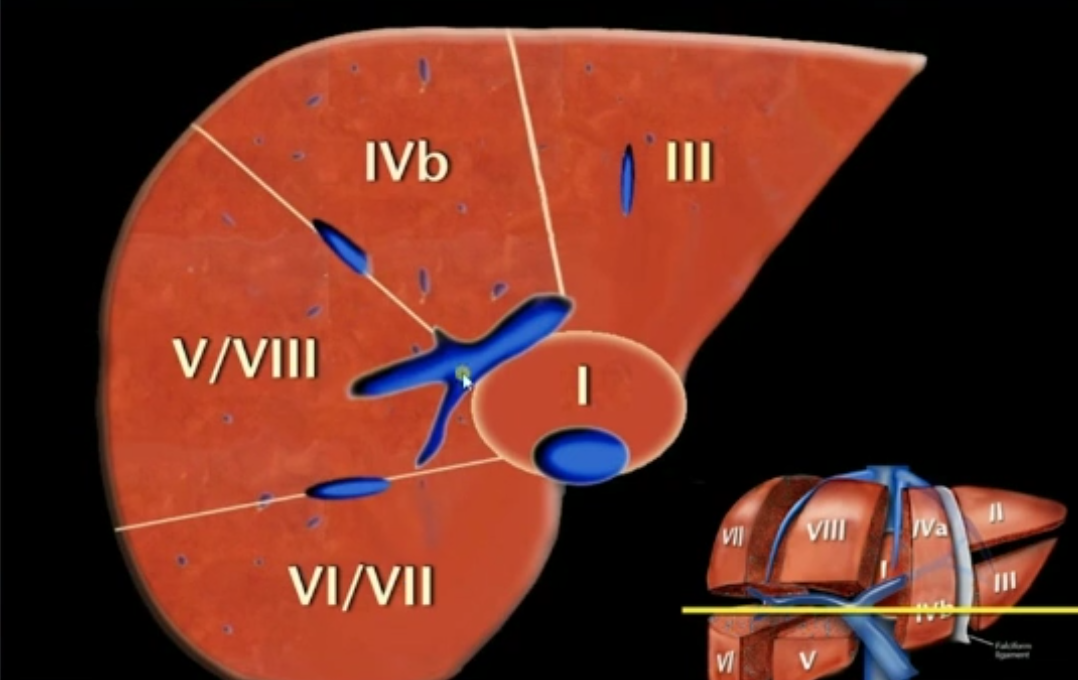

bismuth分段

- 纵向中肝静脉分左右,右肝静脉分右前后,镰状韧带分左内外

- 从右到左:右肝后(右肝静脉)右肝前(中肝静脉)左肝内(镰状韧带)左肝外

- 纵向门静脉左右支分上下两份

中心1,其他顺时针标号

解剖标记

- 第一肝门上方中肝静脉,右肝静脉

- 门静脉左支分左肝上下

- 门静脉右支分右肝上下

- 顺时针在片子里是左到右